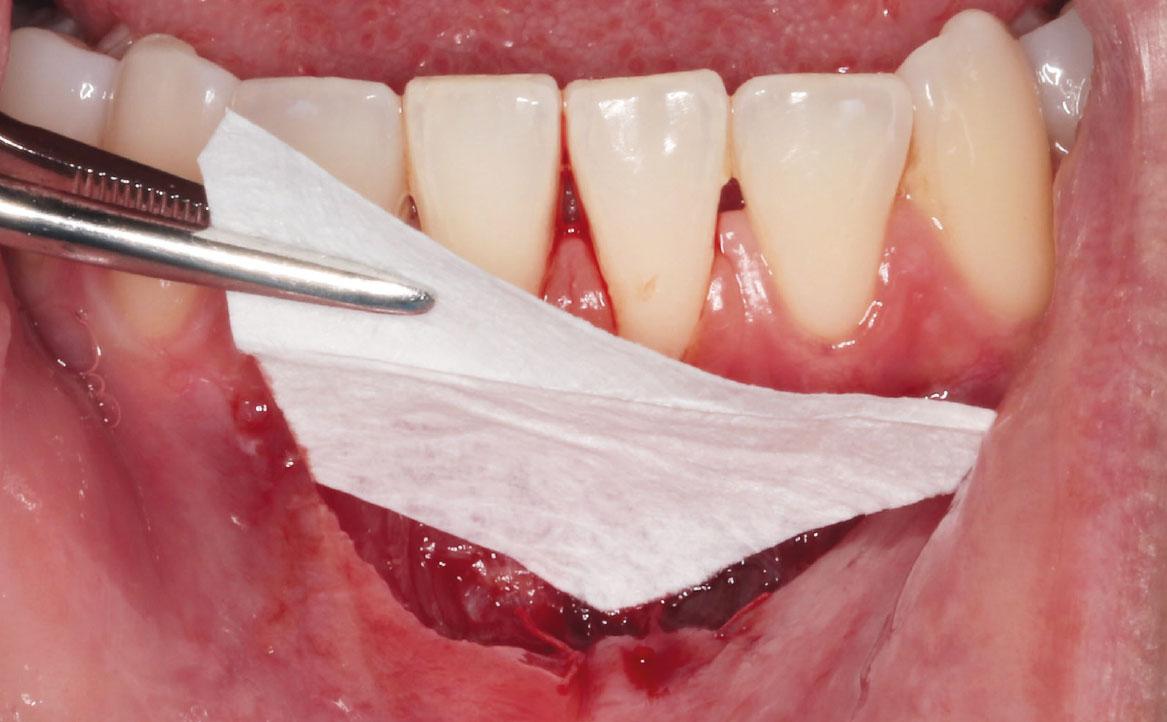

Infine, una membrana riassorbibile in pericardio suino è stata modellata secondo la forma della ferita (fig. 8) e, dopo averla idratata in soluzione fisiologica, è stata posizionata sul sito chirurgico (fig. 9) fissata con punti di sutura riassorbibili (fig. 10). La membrana riassorbibile in pericardio suino è un materiale reso altamente biocompatibile grazie ai processi di rimozione di cellule e lipidi eseguiti con anidride carbonica supercritica (14). La membrana svolge un’azione barriera separando la ferita chirurgica dall’ambiente del cavo orale. Inoltre, favorisce l’adesione cellulare e ricopre un importante ruolo nella promozione della formazione e della stabilizzazione del coagulo (15,16). Studi condotti sull’effetto combinato dell’acido ialuronico reticolato e della membrana riassorbibile in pericardio suino dimostrano un rallentamento della degradazione della membrana e un potenziamento degli effetti del glicosamminoglicano (17).